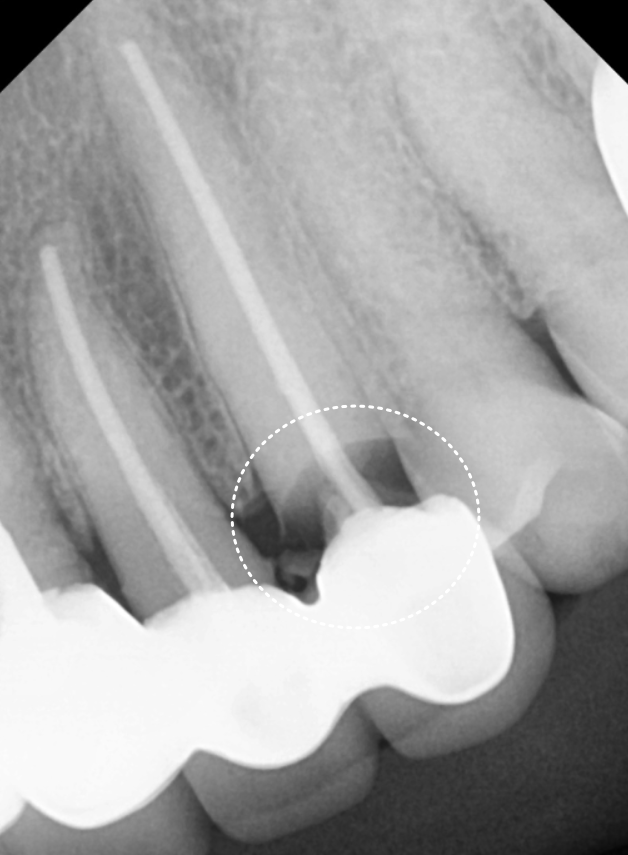

방사선 사진과 CT를 확인해보니

오래된 보철물 안쪽으로

2차 충치가 심하게 진행되어 있었고,

240315

특히 왼쪽 송곳니(#23)는 이미 치아 머리 부분이

부러져 뿌리와 분리된 상태였습니다.

뿌리 끝까지 염증이 퍼져

잇몸뼈가 많이 녹아있었기에,

안타깝게도 발치를 진행하기로 했습니다.